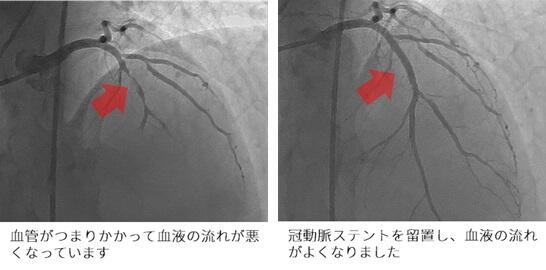

カテーテル治療では、バルーン(風船治療)やステントで狭窄した血管を広げ、血流を改善します。

当院でカテーテル治療を行った急性心筋梗塞の一例